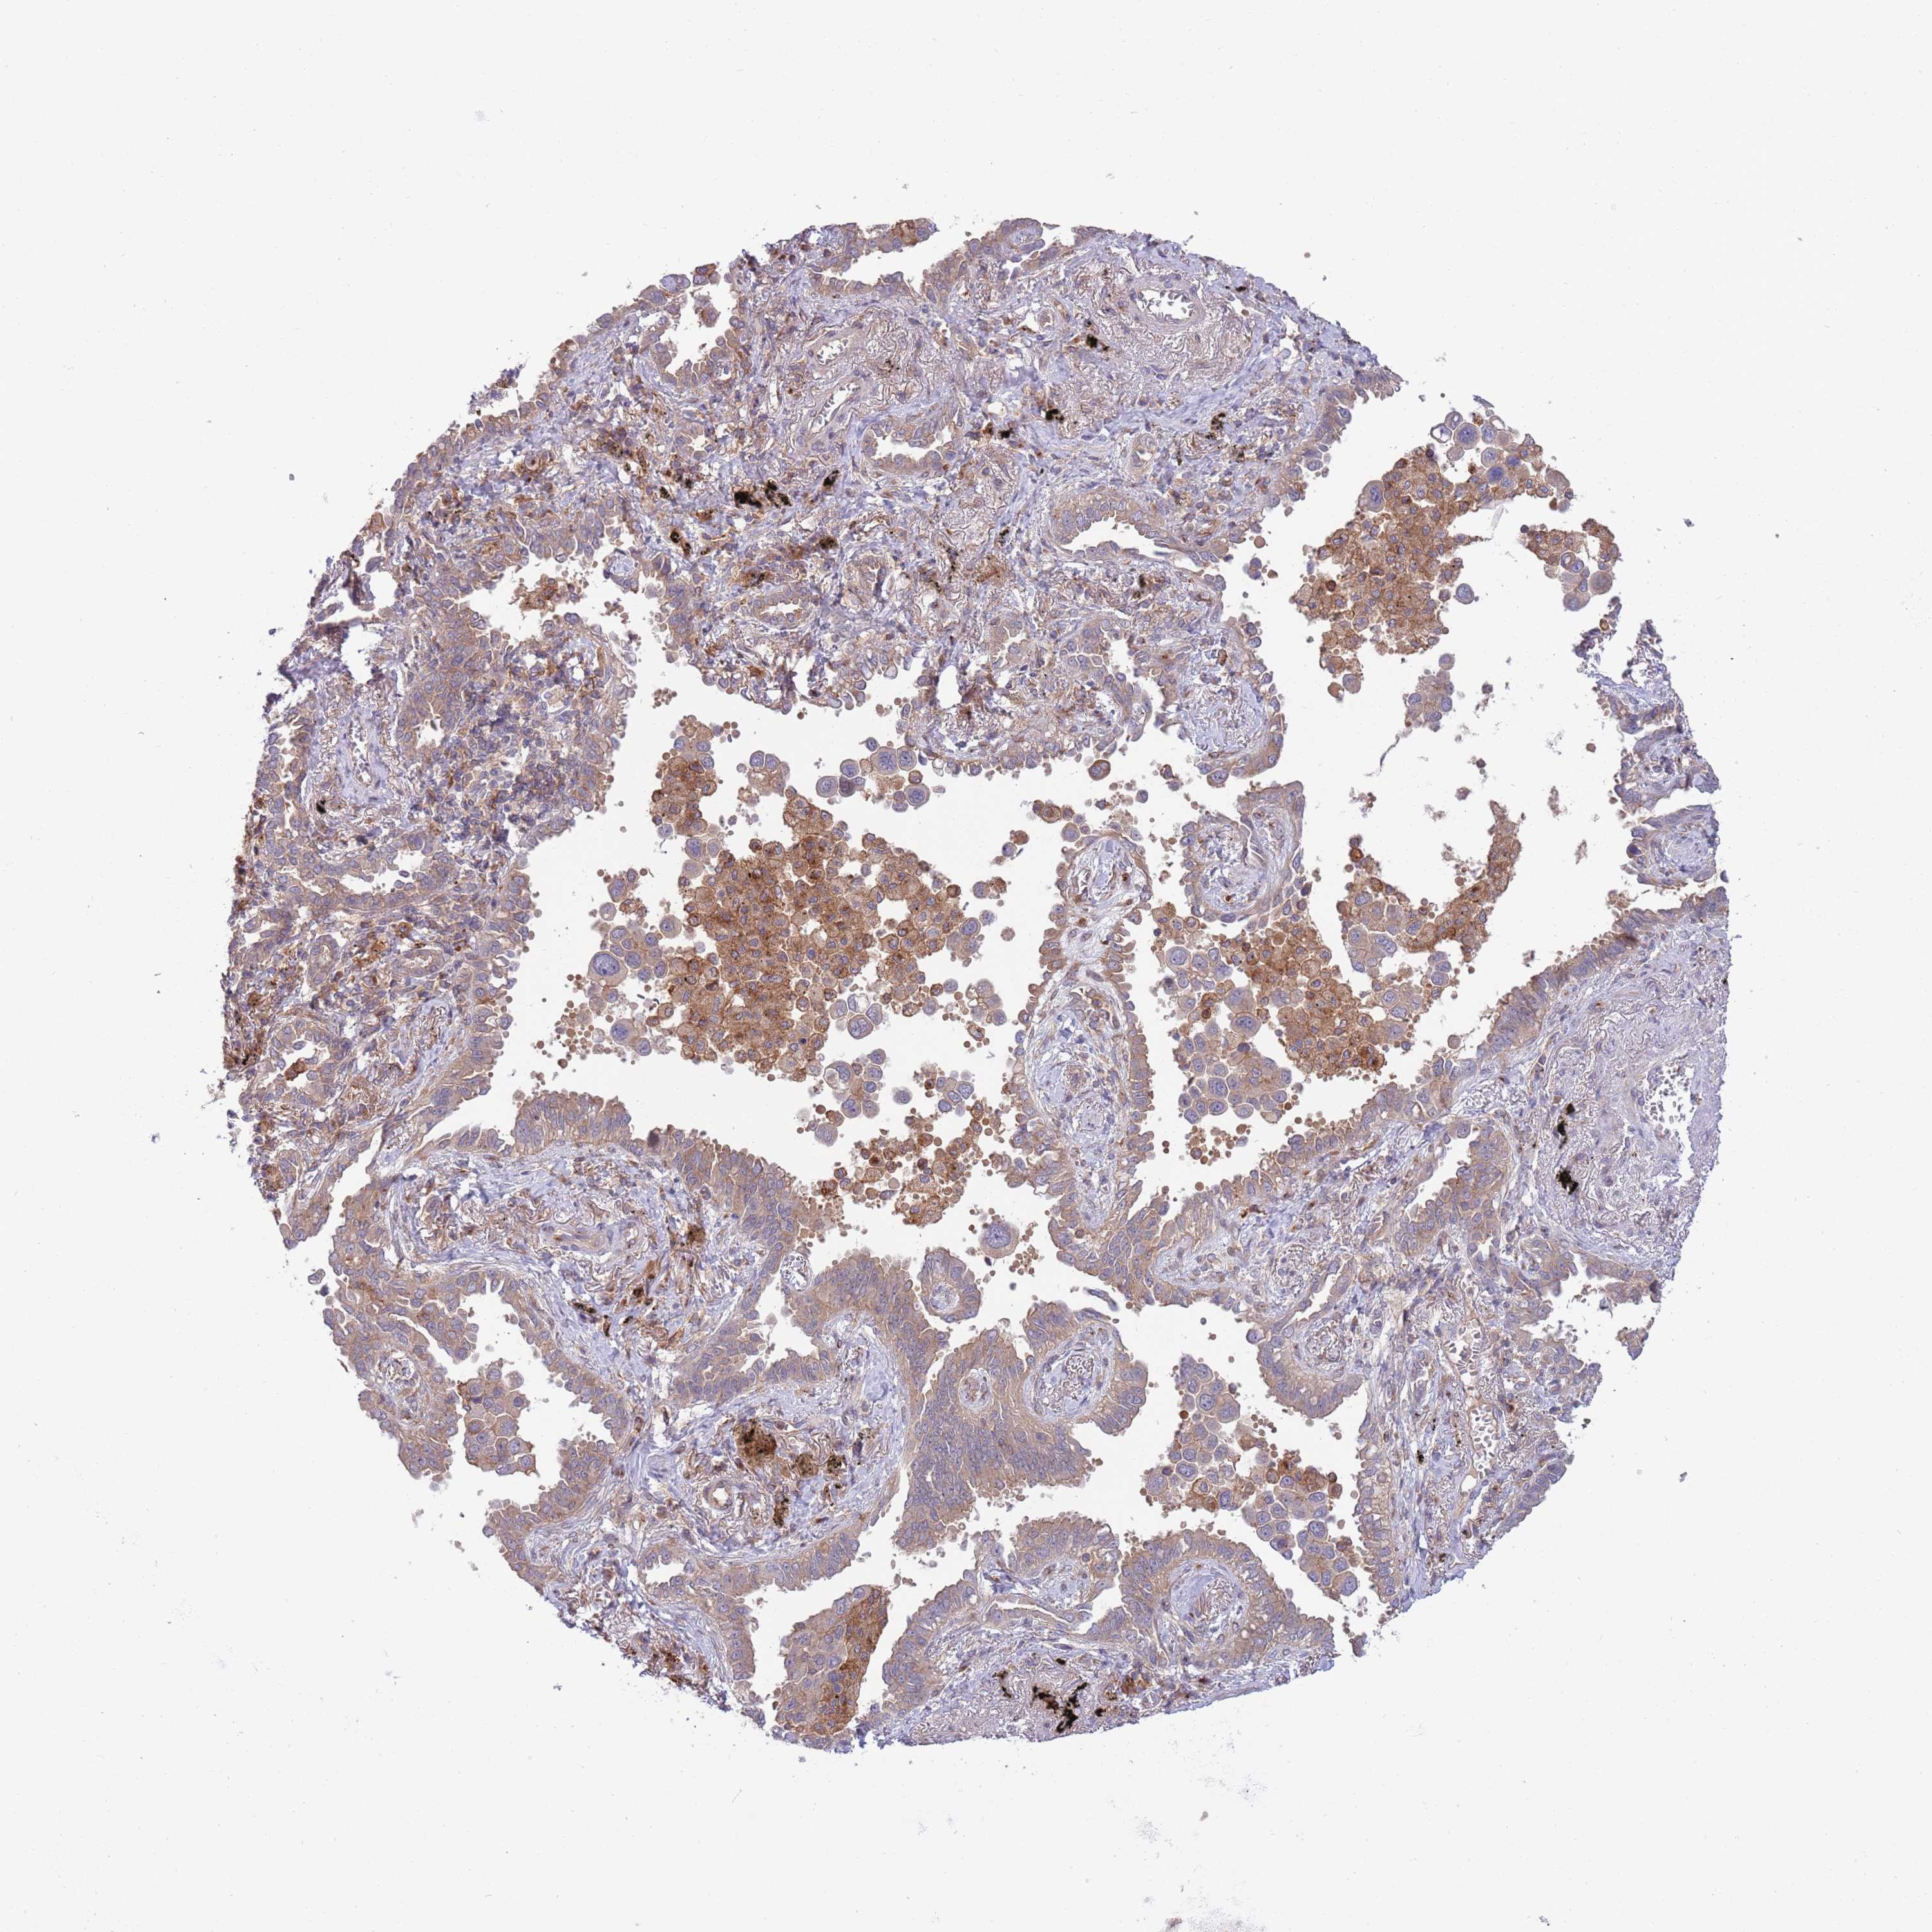

CANCER LUNG CANCER Show tissue menu

Lung cancer

Human cancer